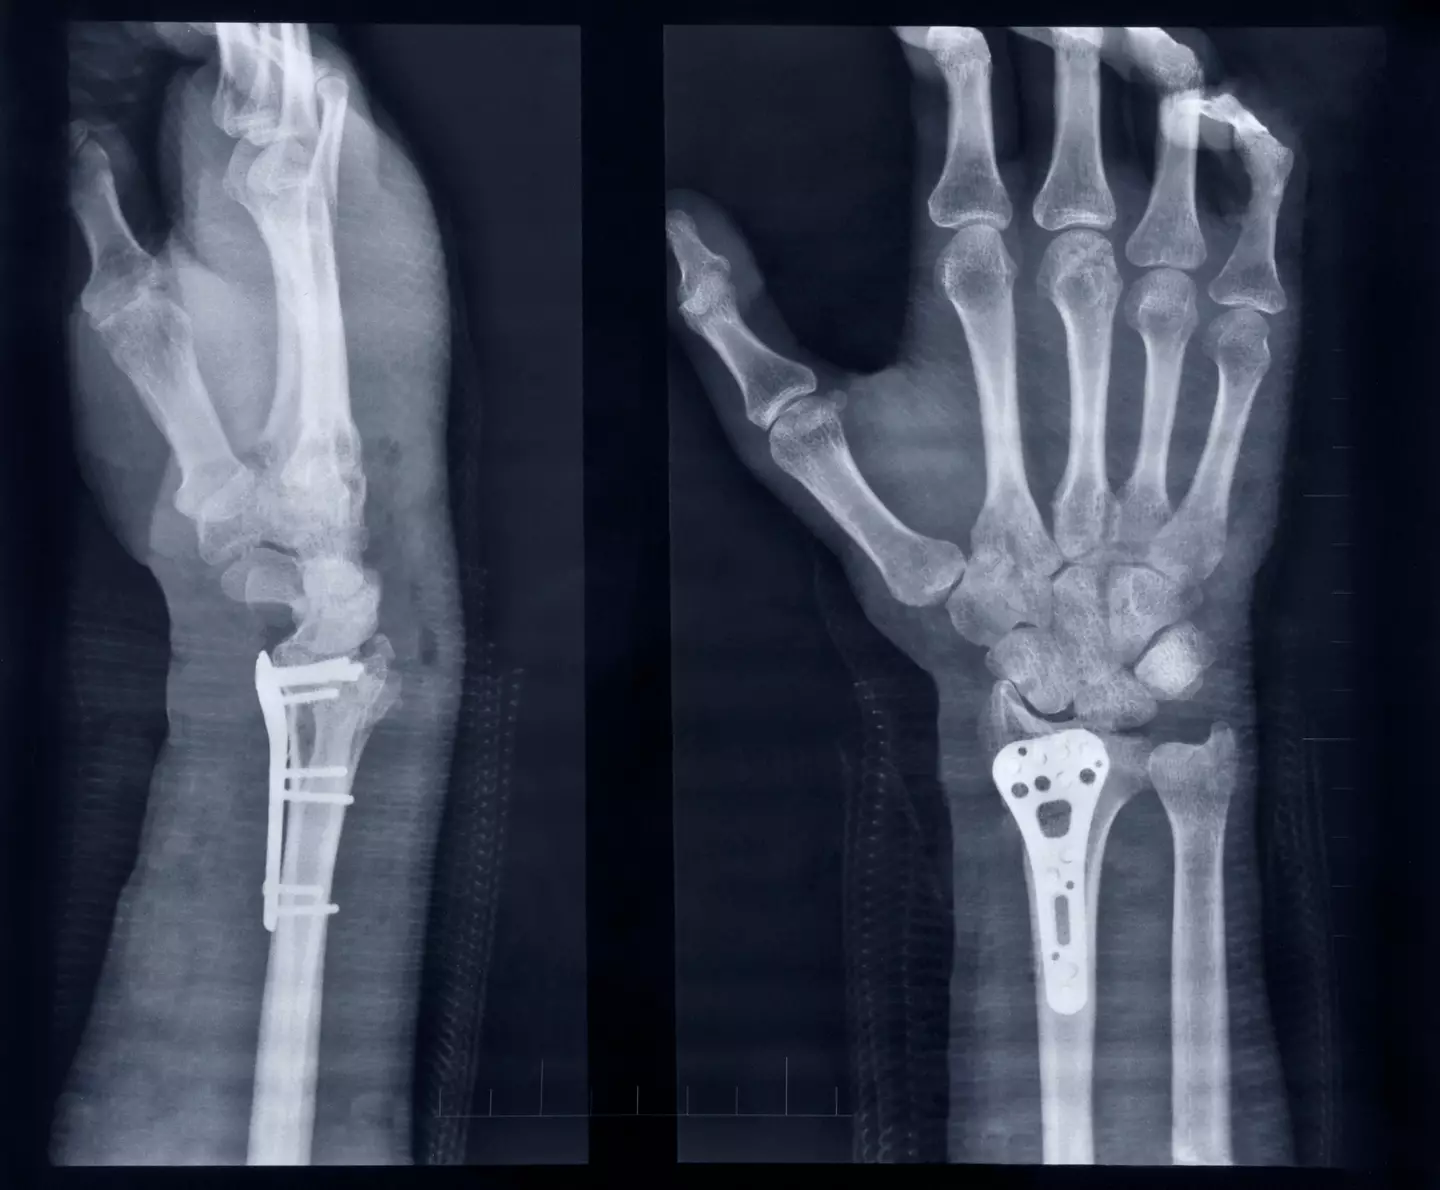

In a notable trial, Bone-02 was used to repair a severe wrist fracture in under three minutes.

After three months of recovery, the patient’s fracture healed completely without complications, restoring full wrist functionality.